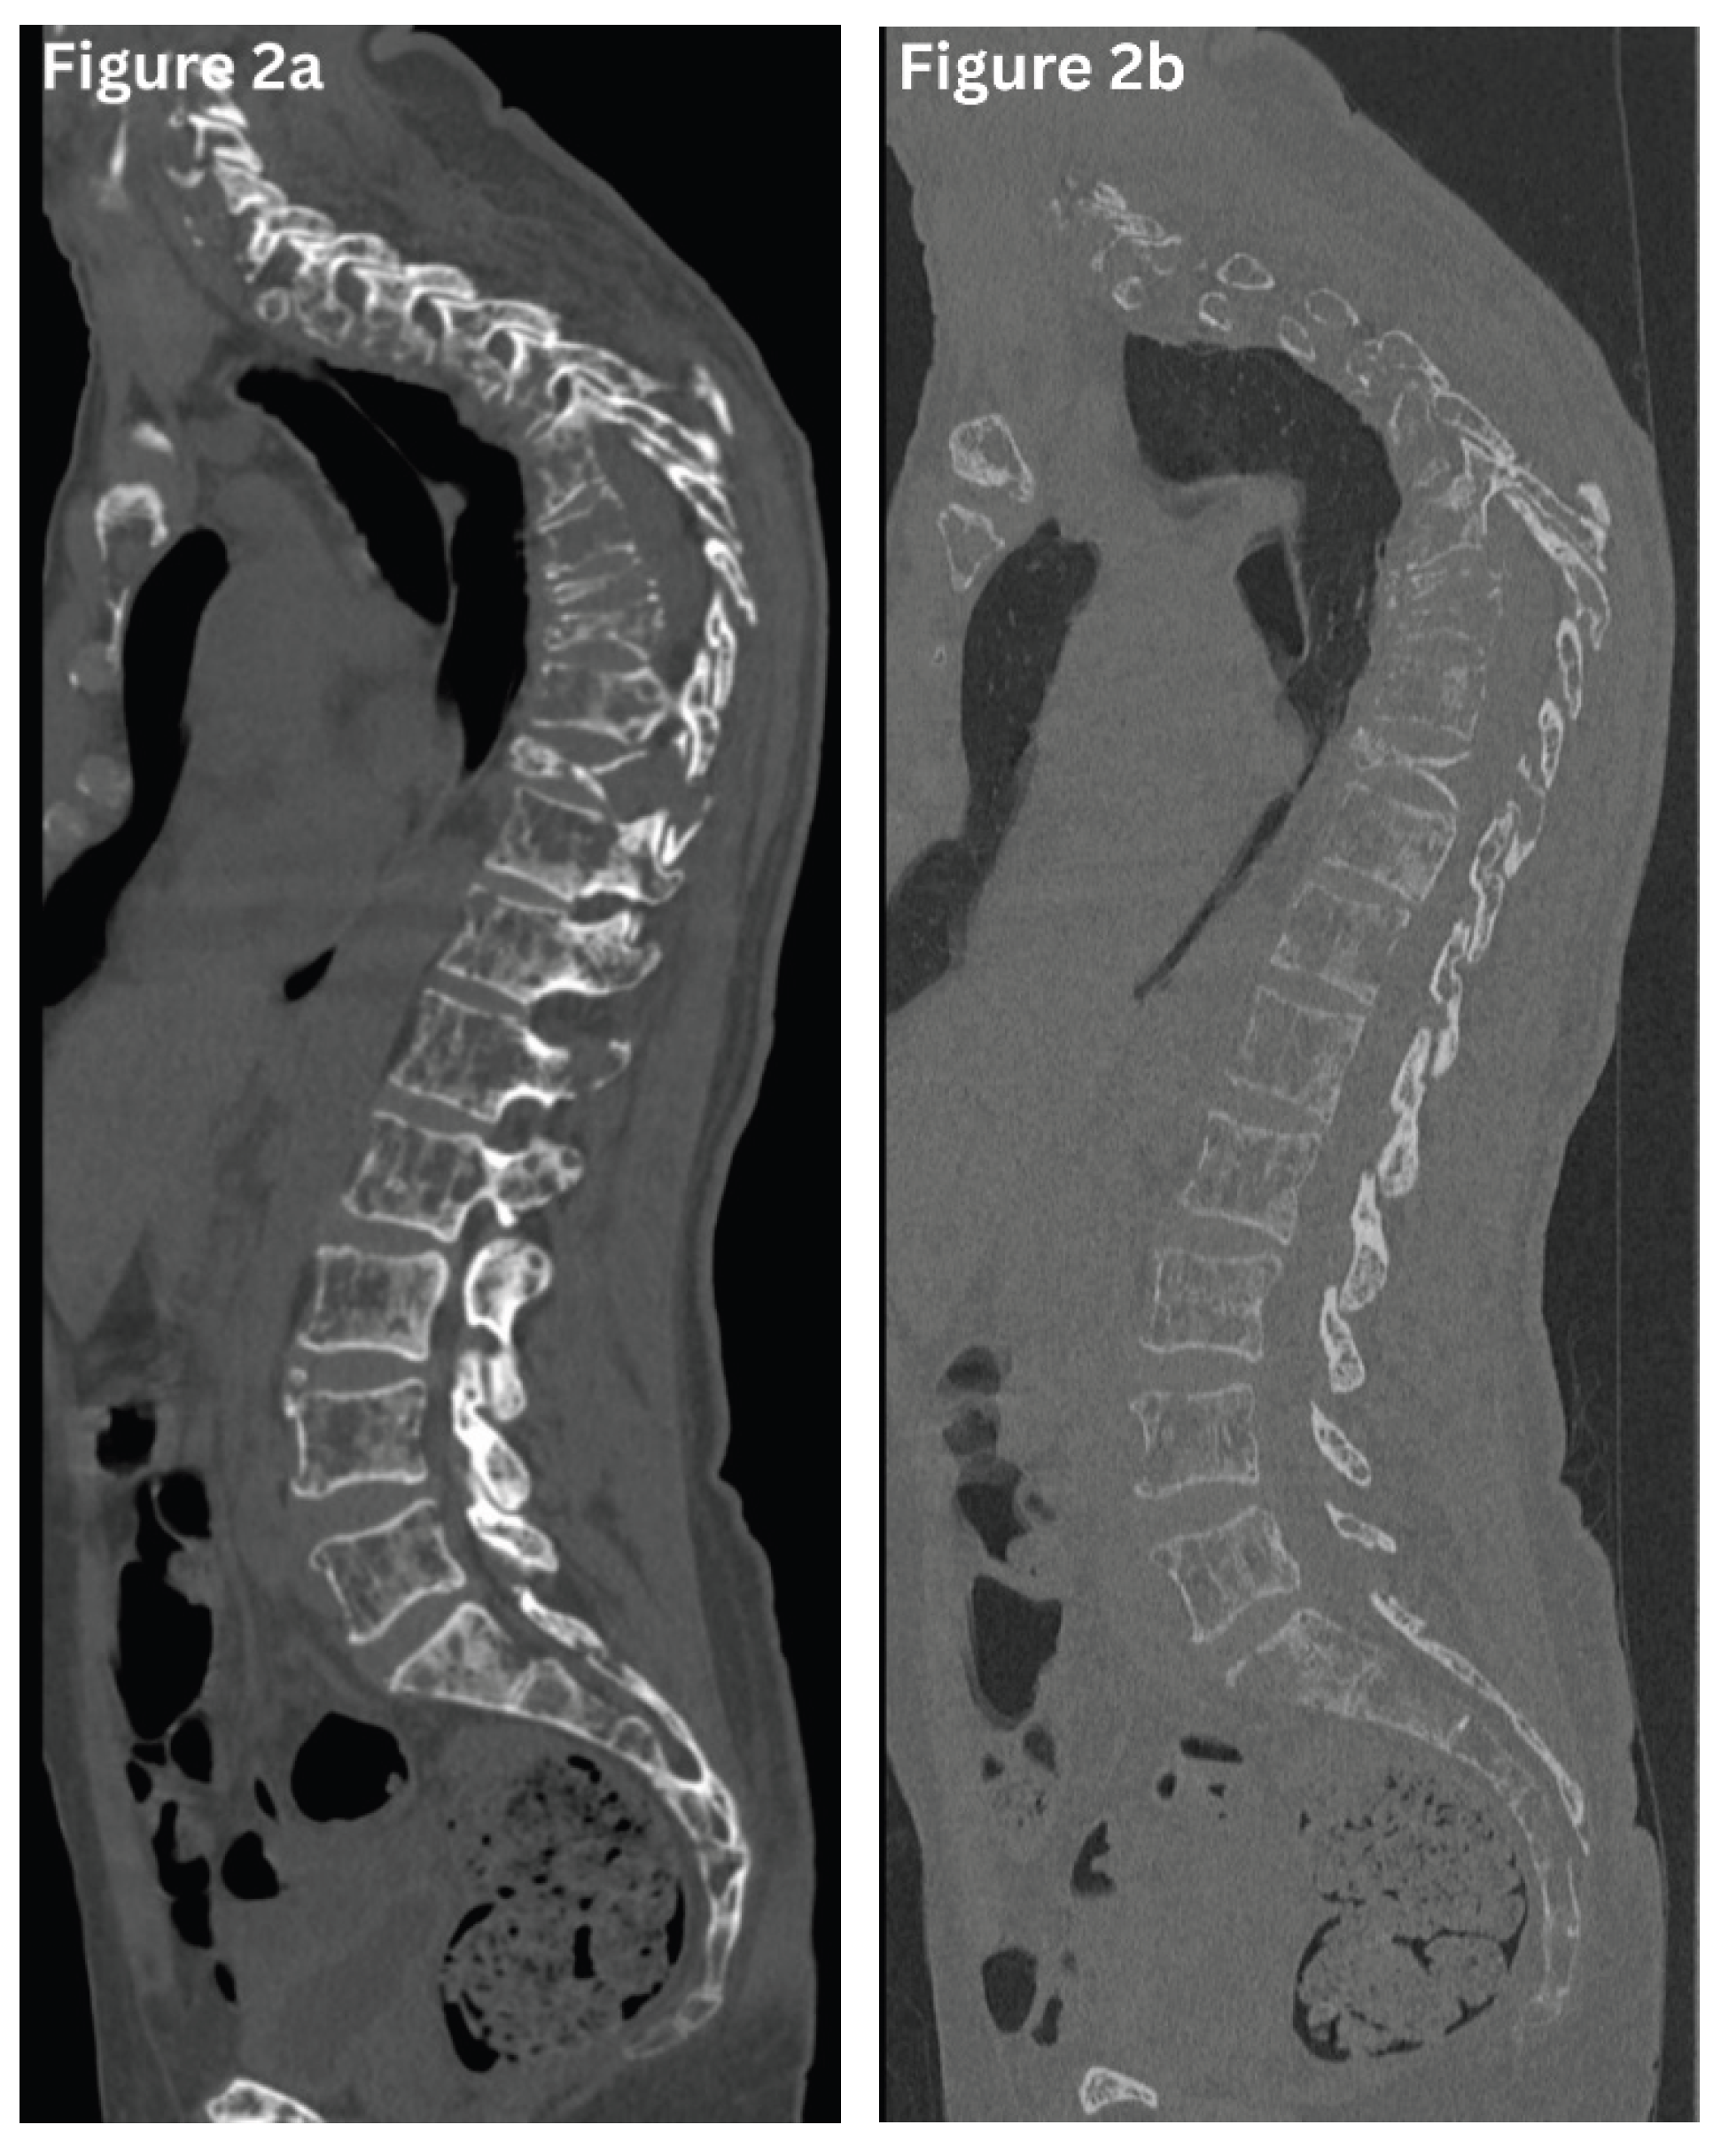

T1W images show marrow with low signal (hypointense) in acute fractures, while STIR or fat-saturated T2 sequences demonstrate marrow oedema (hyperintense), confirming the acuity. (Figure 3) Chronic fractures often lack marrow oedema and may exhibit fatty replacement.

Benign osteoporotic fractures typically exhibit band-like low signal intensity on T1 and T2 images along the endplate, with spared posterior elements and normal adjacent discs. Malignant fractures, in contrast, exhibit diffuse marrow replacement, convex posterior vertebral borders, epidural or paraspinal soft-tissue components, and involvement of the posterior elements or multiple contiguous vertebrae.

Figure 3. a-c. Sagittal MRI of the thoracolumbar spine demonstrates significant compression fractures involving the T12 and L1 vertebral bodies. Retropulsion of the T12 vertebral body is noted, resulting in mild compression of the lower spinal cord. The affected vertebrae exhibit low signal intensity on T1-weighted images (Figure 3a), accompanied by high signal intensity on T2-weighted images (Figure 3b) and STIR sequences (Figure 3c), consistent with acute vertebral compression fractures.